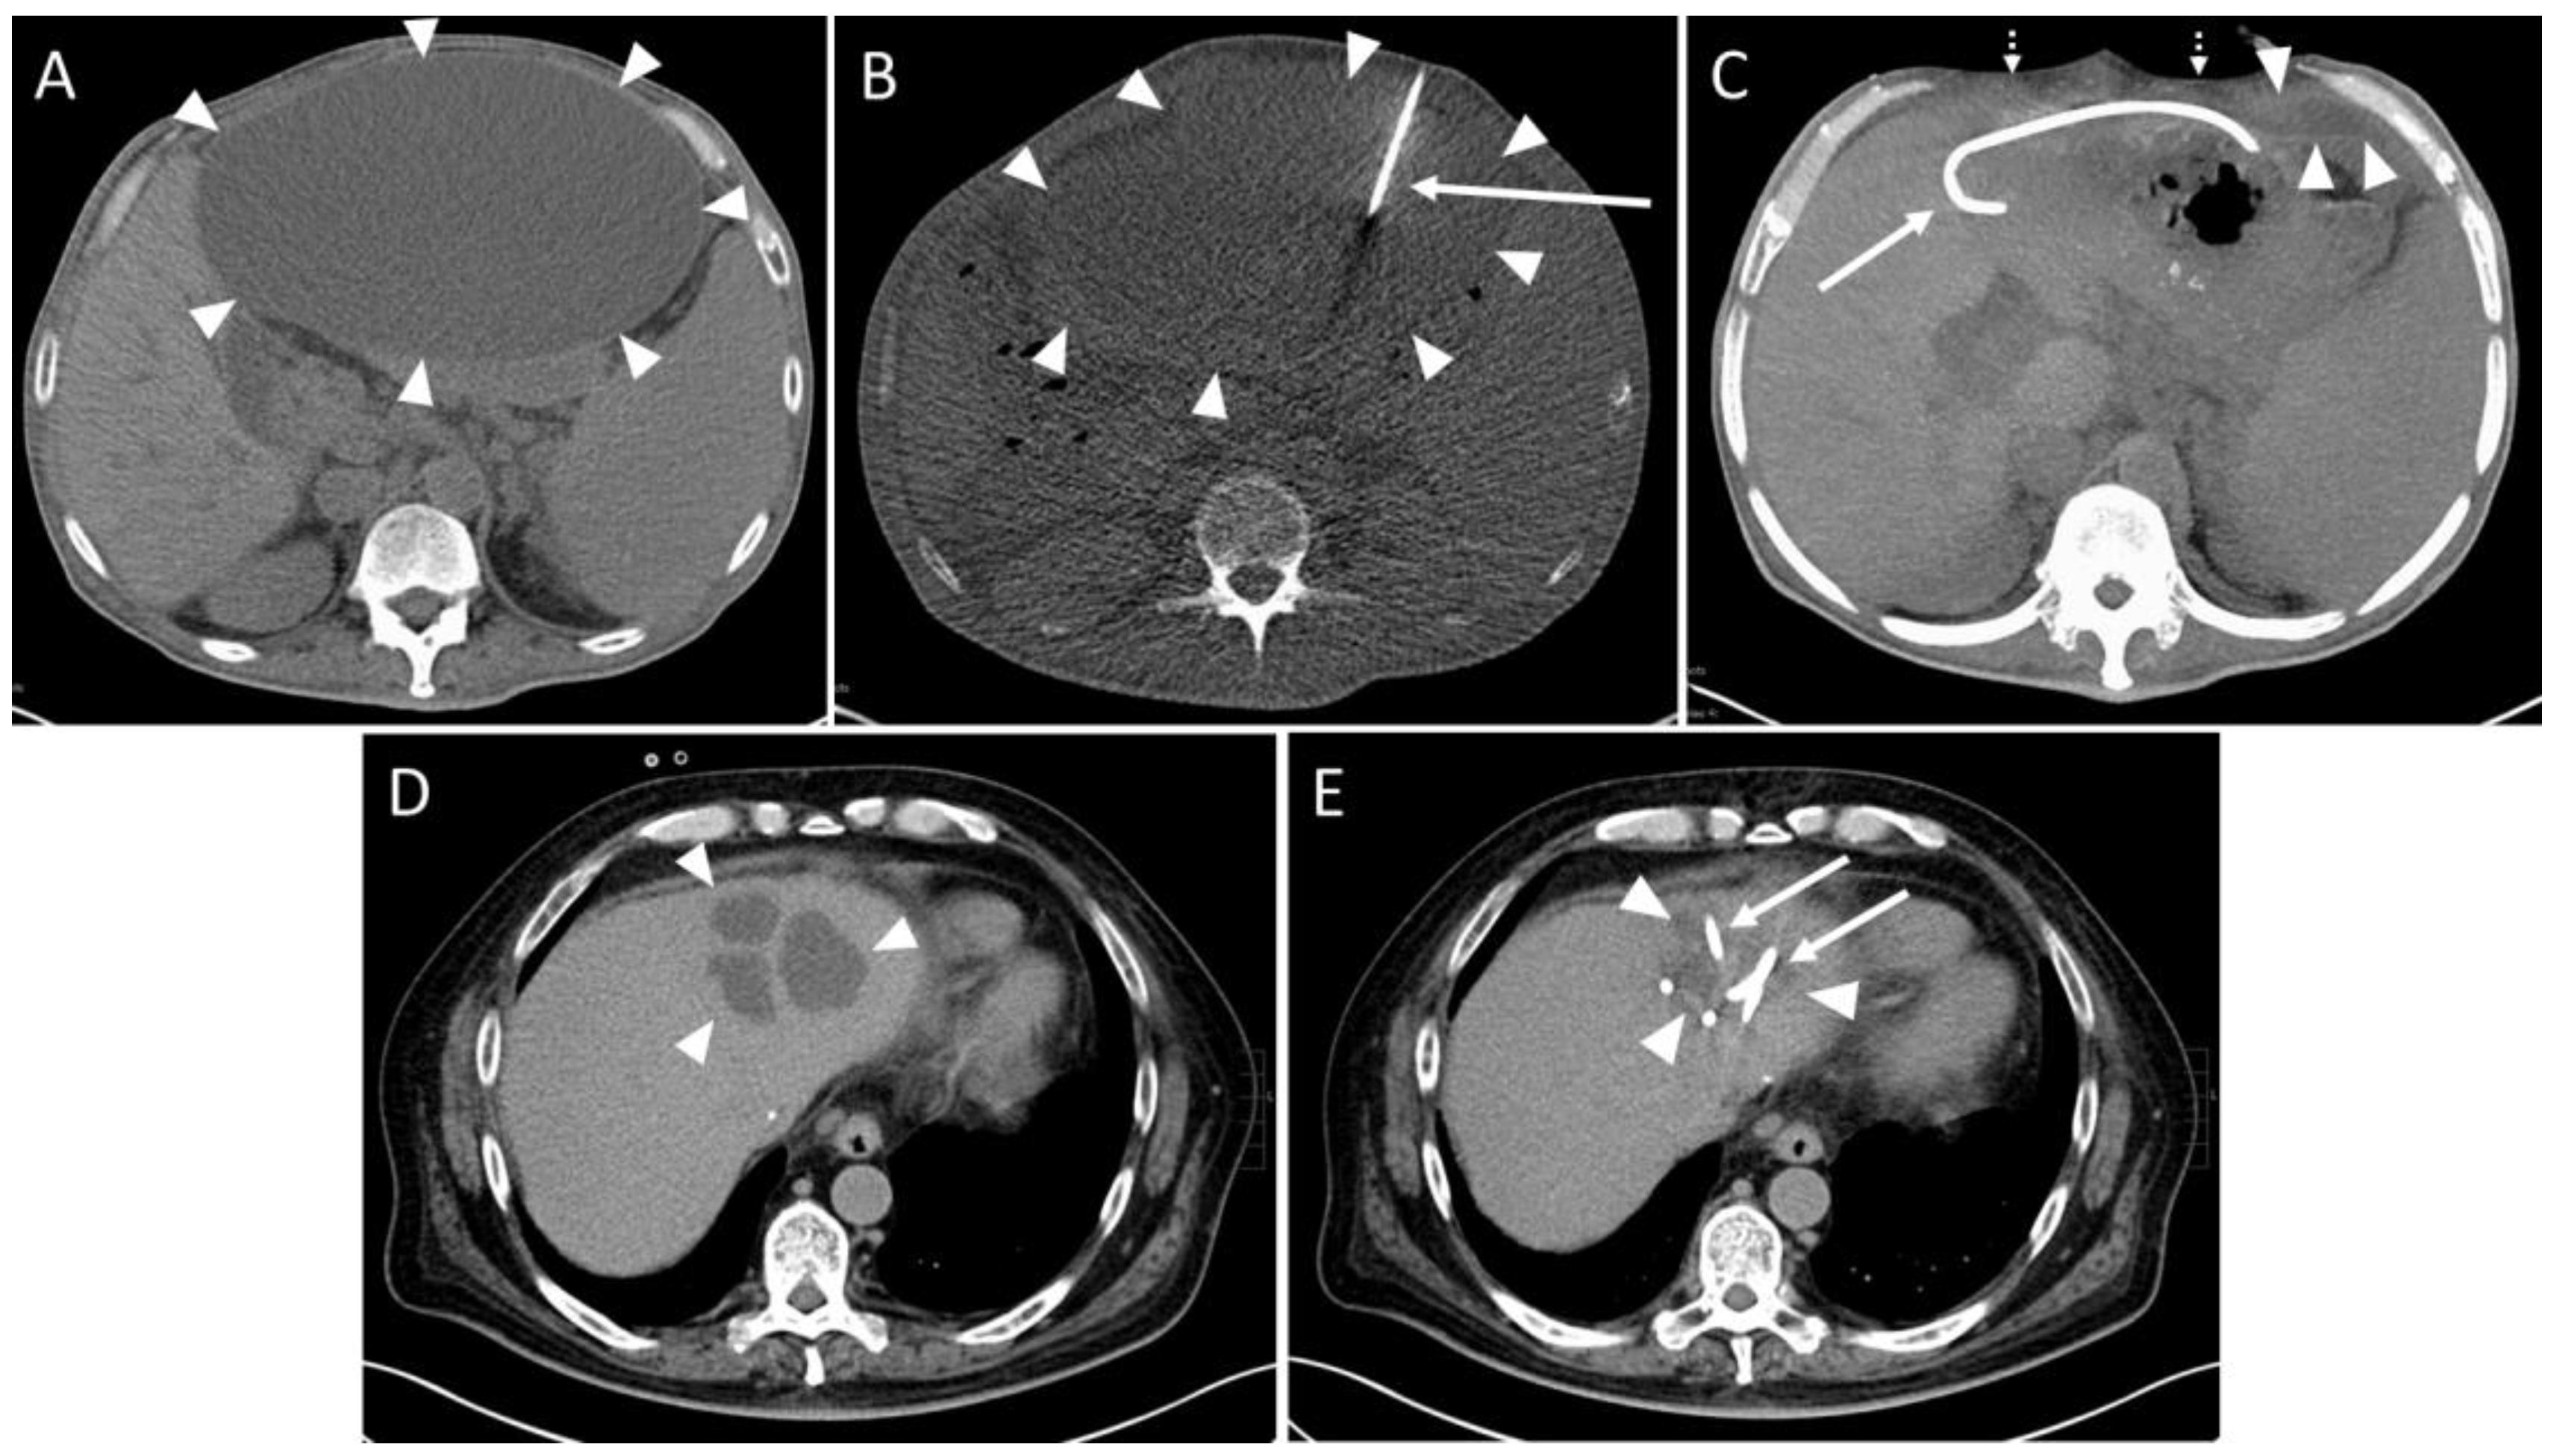

Figure 2. Example of a routine CT-guided drainage placement without complications. A 50-year-old man with history of liver transplantation due to alcohol-induced cirrhosis. Five weeks after surgery, an increase in transaminases and serum bilirubin was observed. Later, a palpable mass and upper abdominal pain developed. (A) CT planning scan 59 days after transplantation showed a large subcapsular fluid collection with mass effect encompassing the anterior liver margin (arrowheads). (B) CT fluoroscopy scan: An 8F drain (arrow) placement in the collection (arrowheads) via a left anterior transabdominal access using the Trocar technique was performed. (C) Maximum-intensity projection (25 mm slab thickness) of the CT control scan revealed a marked reduction in the mass effect. It was possible to aspirate 3000 mL of yellow-green fluid, resulting in almost complete drainage of the formation. Only a small residue (arrowheads) remained in the left recessus. Patient reported instant relief of symptoms (dotted arrows: collapsed abdominal wall, arrow: drain). No signs of complications such as organ penetration or bleeds are visible. Microbiological analysis revealed a sterile biloma. (D) Eight years later, the patient was readmitted due to cholangitis of the left liver lobe with several abscesses (arrowheads). (E) Again, CT-guided placement of two drains (arrows) could be successfully performed. The additional administration of pathogen specific antibiosis led to a decrease in inflammatory parameters. Arrowheads: Abscesses.